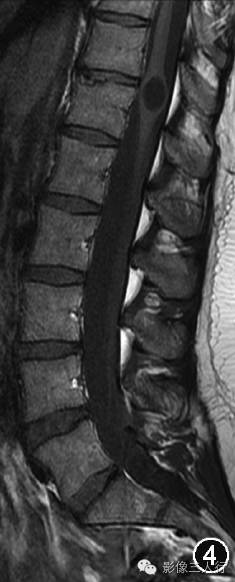

图4~7 男,45岁。腰椎MRI显示第五脑室是位于脊髓圆锥内且囊壁光滑的囊腔,囊腔内的脑脊液在矢状面T1WI上呈低信号(图4),在横断面T1WI上呈低信号(图5),在矢状面T2WI上呈高信号(图6),在横断面T2WI上呈高信号(图7)。所有图片均由加拿大渥太华大学渥太华医院Carlos Torres教授提供